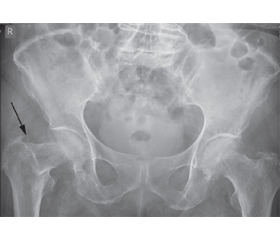

Ризики виникнення перелому у вертлюговій ділянці стегнової кістки у період перебування пацієнтів старшої вікової групи на стаціонарному лікуванні корелюють з такими під час амбулаторного чи домашнього спостереження. Пацієнти неврологічного профілю мають значну схильність до травмування. Щорічно в усьому світі реєструється близько 1 700 000 випадків переломів проксимального відділу стегнової кістки, а ризик виникнення перелому у вертлюговій ділянці протягом життя у чоловіків становить 6 %, у жінок сягає 18 %. Смертність протягом першого року після травми при консервативному лікуванні досягає 56,3 %. Переломи головки стегнової кістки прийнято систематизувати за класифікацією переломів і вивихів AO. Наші статистичні дані за майже двадцятирічний період практичної діяльності дозволяють проаналізувати найбільш часті причини госпітальних переломів шийки стегнової кістки, серед яких можна виділити насамперед недостатній контроль рухових, постуральних й координаторних порушень з боку молодшого медичного персоналу, який забезпечує професійний догляд за хворим. Найбільш об’єктивна шкала для оцінки ризику падіння — це шкала падіння Морса. У статті наведено клінічний випадок госпітального перелому шийки стегнової кістки у хворого старшої вікової групи з коморбідною неврологічною патологією. З метою зменшення ризику падіння хворих в умовах медичного закладу з непередбачуваним результатом рекомендуємо такі профілактичні заходи: обов’язкове тестування кожного пацієнта на ризик можливого падіння; при середньому і високому рівні ризику падіння — забезпечення хворого індивідуальним постом молодшого медичного персоналу; облаштування приміщень медичного закладу всіма необхідними технічними засобами для безпечного перебування пацієнта; у разі падіння хворого — негайне виконання клінічного протоколу із залученням відповідних служб.

The risks of acetabular fractures during hospital treatment in patients of the older age group correlate with those during outpatient or home care. The neurological patients have a significant ability to injury. Every year, about 1,700,000 cases of proximal femur fractures are recorded worldwide. The risk of fracture in the acetabular region during the life is about 6 % in men and reaches approximately 18 % in women. Mortality within one year after injury reaches 56.3 % under conservative treatment. Femoral head fractures are usually systematized according to the AO Fracture and Dislocation Classification. Our statistical data for almost twenty years of practical experience allows us to analyze the most frequent causes of hospital femoral neck fractures. We should distinguish, first of all, insufficient control of motor, postural and coordination disorders by nurse-caregivers who provide professional care for the patient. The most objective scale to assess the risk of falling is the Morse Fall Scale. The article presents a clinical case of the hospital femoral neck fracture in a patient of the older age group with comorbid neurological pathology. In order to reduce the risk of patients’ falling with an unpredictable outcome during hospital stay, we recommend the following preventive measures: mandatory testing each patient for the risk of a possible fall; with an average and high risk of falling — providing the patient with an individual nurse-caregiver station; equipping the premises of the medical facility with all necessary technical means for the patient’s safe stay; in case of a patient’s falling — immediately implement the clinical protocol with the involvement of relevant services.